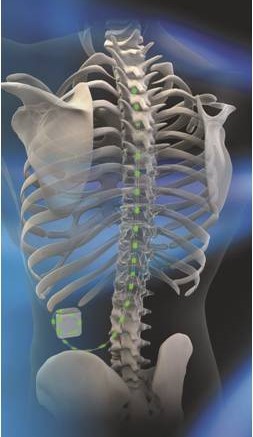

Η μέθοδος διέγερσης του νωτιαίου μυελού στηρίζεται στη μετάδοση ηλεκτρικών παλμών μέσω ηλεκτροδίων που τοποθετούνται στον επισκληρίδιο χώρο της σπονδυλικής στήλης. Οι παλμοί αυτοί μεταδίδονται μέσω γεννήτριας, παρόμοιας ενός βηματοδότη, η οποία εμφυτεύεται υποδόρια στην κοιλιακή χώρα. Στόχο της διέγερσης του νωτιαίου μυελού αποτελούν οι νευρώνες που εμπλέκονται στην διαβίβαση και στην επεξεργασία του πόνου. Η θεραπεία ενεργοποιεί νευρωνικά κυκλώματα αναστολής του πόνου, προκαλώντας αντικατάσταση του αισθήματος πόνου από ένα ήπιο αίσθημα καύσους ή νυγμού.

Για την εμφύτευση του συστήματος απαιτούνται δύο στάδια με μεσοδιάστημα 10-15 ημερών. το πρώτο στάδιο αφορά στη δοκιμαστική περίοδο, ενώ το δεύτερο στην τελική εμφύτευση.

Με τον ασθενή σε πρηνή θέση και με ελαφρά καταστολή, τα επισκληρίδια ηλεκτρόδια που έχουν ήδη εμφυτευθεί συνδέονται κάτω από συνθήκες πλήρους αποστείρωσης με την γεννήτρια μέσω συνδετικού καλωδίου. Η γεννήτρια εμφυτεύεται υποδορίως στο πρόσθιο ή πλάγιο κοιλιακό τοίχωμα. Κατά τη διάρκεια της διαδικασίας, θα πρέπει να μπορεί ο ασθενής να επιβεβαιώσει τη σωστή κάλυψη των επώδυνων περιοχών.